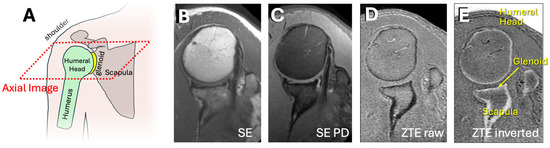

Computed tomography (CT) is the current gold standard for bone imaging in 3D [6,8,9,10]. While preferred for the lack of ionizing radiation, conventional magnetic resonance imaging (MRI) sequences (Figure 1A,B, provided as examples) have suboptimal contrast (i.e., bone has a similar signal to several other tissues) for distinguishing bone for visualization [9]. However, recent advances in MRI including ultrashort time-to-echo (UTE) [11,12] and zero time-to-echo (ZTE) techniques [13,14,15,16] have shown to be promising alternatives that can depict cortical bone with a uniform contrast (i.e., a low signal for the cortical bone and the air/back ground, a high signal for all other tissues such as muscle and trabecular bone and marrow; Figure 1C), making it relatively easy to isolate and visualize the bones [14,17], with minor processing. Unlike conventional magnetic resonance (MR) images that depict cortical bones and other soft tissues (such as ligaments) with low signal intensity (Figure 1A,B), ZTE MRI provides a more uniform contrast for bone, for example with a high signal intensity in inverted ZTE images (Figure 1D). These studies have also shown that cortical bone morphology (e.g., surface contour) measured on UTE or ZTE are highly similar to that measured on a CT or a micro CT [17]. For these reasons, ZTE MRI is increasingly being prescribed when bone imaging is desired [17].

Figure 1.

(A) Anatomy of the shoulder showing the major bone structures of the humerus, humeral head, glenoid, and scapula. The axial imaging plane is shown in the dotted red box. Conventional shoulder MR images were acquired using conventional (B) spin echo proton density weighted, (C) spin echo proton density weighted with fat suppression, and (D) zero echo time (ZTE) sequences. Conventional sequences do not isolate bone effectively. (E) Inverted ZTE image depicting mostly bony tissues with high signal intensity. Conventional magnetic resonance (MR) images depict non-bony tissues with similar contrast as bony tissues, making them less useful for bone-only imaging.